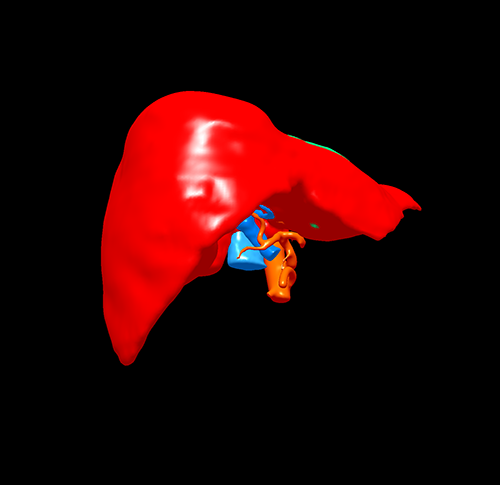

左肝肝癌---扩大左半肝切除+尾状叶切除